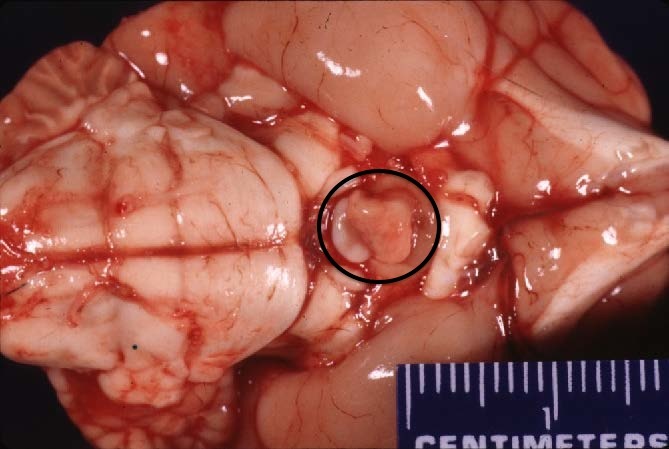

Which part of the brain is indicated by the circle?

pituitary gland